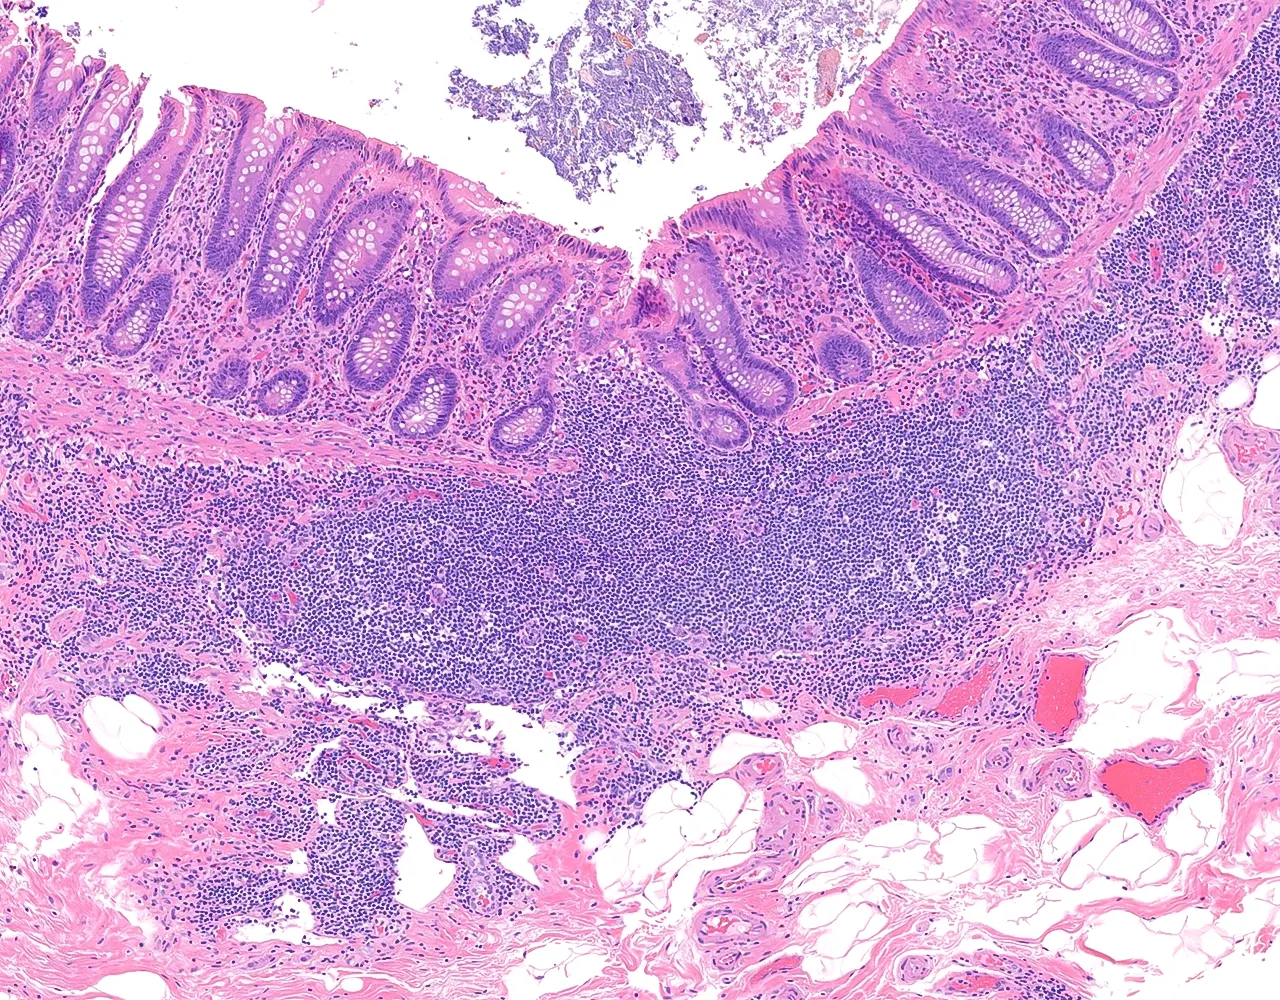

- Le gros intestin est responsable de l’absorption de l’eau et des électrolytes, de la sécrétion de mucus pour la lubrification, de la compaction et du stockage des matières fécales, ainsi que de la contribution aux interactions entre l’hôte et le microbiote.

- L’appendice est un diverticule borgne naissant du caecum.

- Il contribue principalement à la fonction immunitaire locale grâce à son abondant tissu lymphoïde et peut également agir comme réservoir du microbiote intestinal normal.